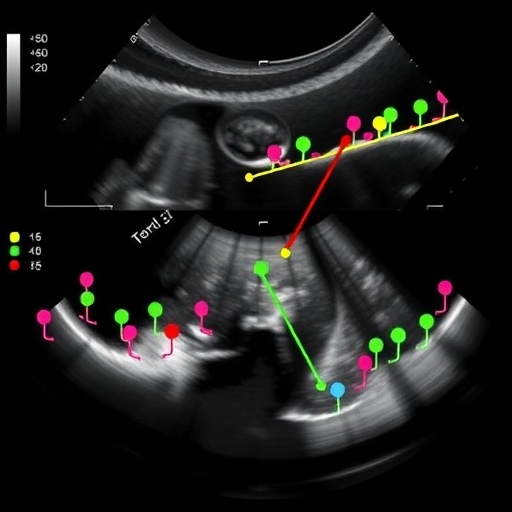

Underpinning this approach is a multi-stage processing pipeline. Initially, raw ultrasound images undergo preprocessing to enhance signal quality and suppress noise artifacts. Enhanced images then enter the object detection network, where candidate regions potentially containing the prostate are proposed. These proposals undergo rigorous refinement and classification to precisely delineate the gland’s boundaries. The end result is a heatmap-based output highlighting the prostate’s location, ready to be overlaid seamlessly onto the original ultrasound scan.

Moreover, the authors also explored the interpretability of their deep learning model. By employing visualization techniques such as class activation mapping, they provided insights into which ultrasound features were most informative for the detection task. This transparency bolsters clinician trust and facilitates integration into clinical practice, where understanding AI decision-making processes remains a critical step for adoption.